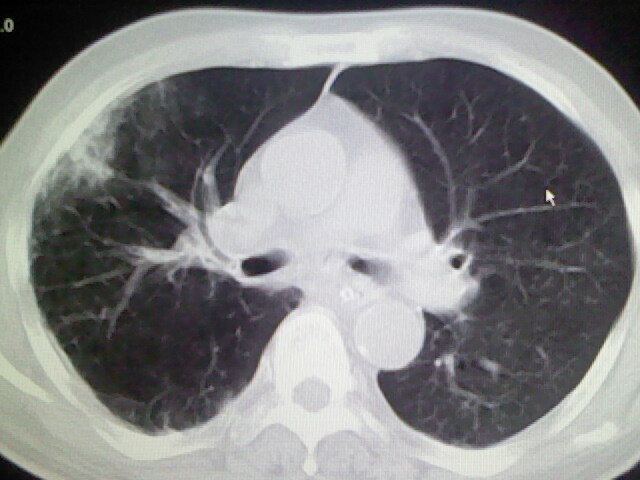

右肺病灶考虑炎症性。

右肺病灶考虑炎症性

考虑右肺及左肺下叶炎症。

右肺及左肺下叶炎症。

考虑右肺及左肺下叶慢性炎症。

右侧肺部见片状密度增高影,边缘模糊。考虑炎症。另食管壁增厚。

右肺肺气肿并炎症。

右肺上叶前段病呈楔形,其尖端指向肺门,考虑肺动脉栓塞可能性大.